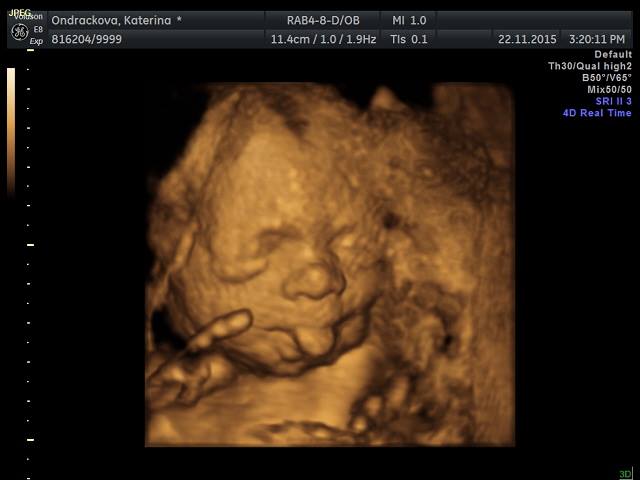

Ja byla na 3D vcera a supr :-) Mame video a 18 fotek. Ze zacatku to vypadalo tragicky, mimi oblicejem zaboreny v placente ale pak ho sestricka nasla z jinyho uhlu. Platila sem neco kolem 1300. Ted je nejlepsi doba na to jit kvuli velikosti mimi a mnozstvi plodovky. Tak sup holky ;-)

Ted su konecne na pc, tak prikladam vcerejsi ulovky